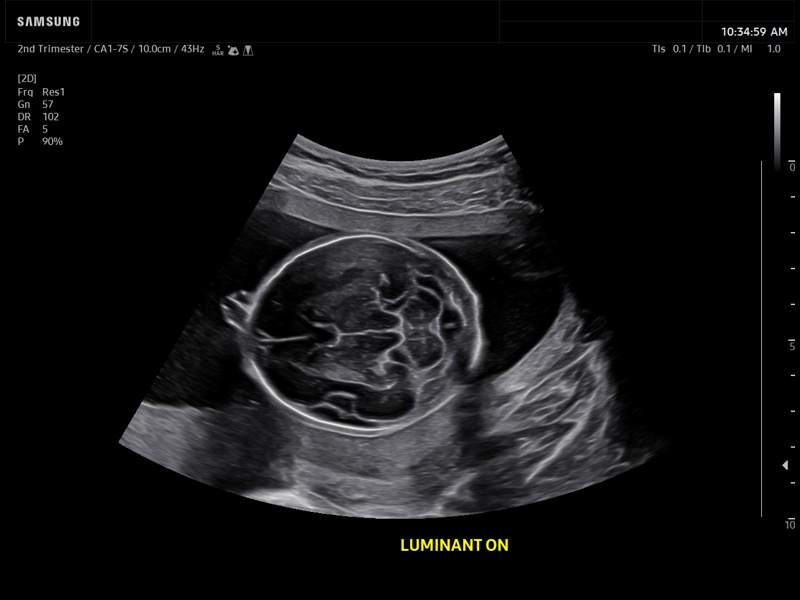

Fetal brain, Luminant™

Fetal brain, Luminant™ (echogramm №933)

[RU] Ultrasound image №933: Fetal brain transcerebellar plane view using Luminant™ (highlighting the boundaries of structures). 2-nd trimester, convex probe 1-7 MHz.

Echogramm was received by ultrasound scanner Z20 (new model).